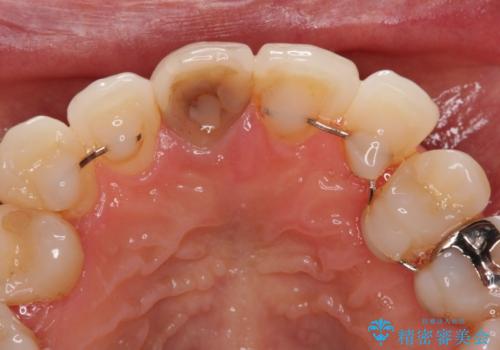

失活により変色した前歯 オールセラミッククラウンによる審美歯科治療

- 前歯の変色を気にして来院された患者様です。

ラミネートベニアによる治療を以前受けていたものの、神経組織が失活して以降、徐々に変色してきたとのことでした。

オールセラミッククラウンにて補綴治療を行うこととしました。